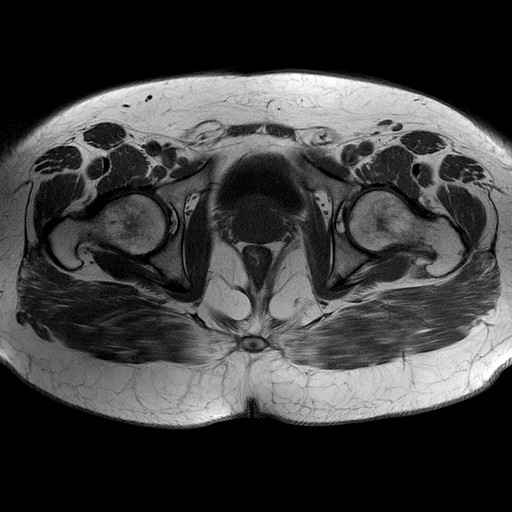

Esami: RMN BACINO

T1W_TSE

Evidenti e simmetriche alterazioni osteofitosiche in regione coxo femorale con riduzione delle rime articolari. Degenerazione completa del cercine glenoideo. Non attuali segni di versamento articolare. Non segni di edema osseo che escludono attuale algodistrofia od osteonecrosi. Lieve e simmetrica riduzione del trofismo della muscolatura glutea.